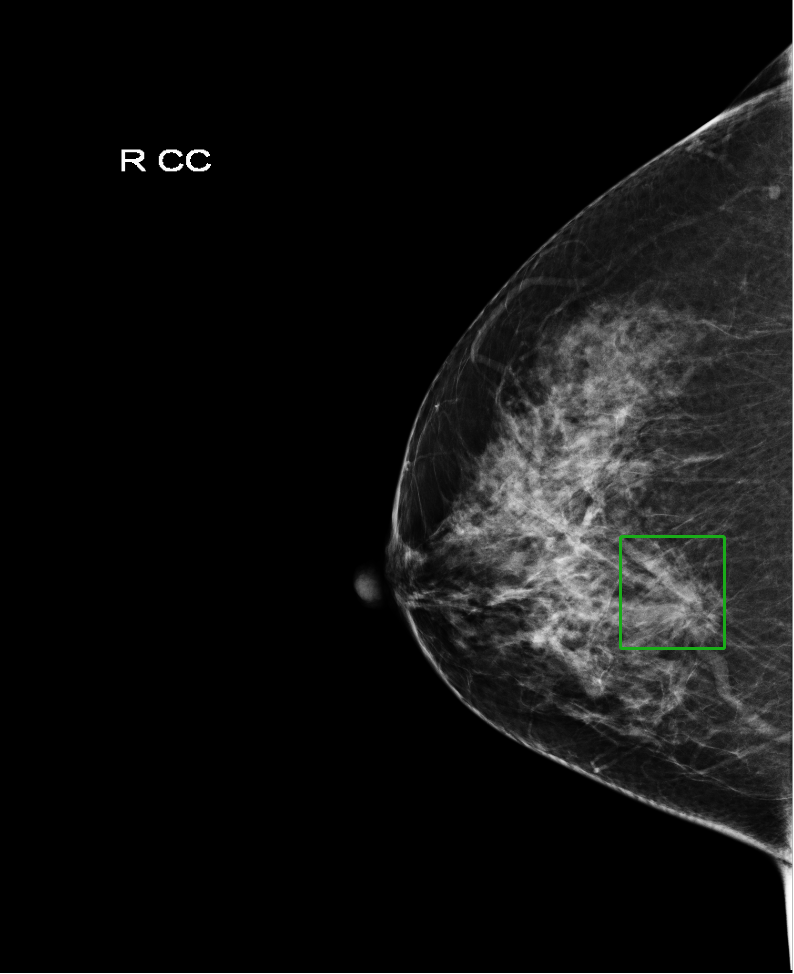

Deep learning object detection algorithm has been widely used in the task of classifying or detecting objects of natural images [3] and [8], and are receiving more and more attentions on its usage in medical image analysis. However, current object detection tasks are all based on the data annotated with object classes and their bounding boxes, those images which are not considered during labeling may contain regions or objects that are similar to the target ones, and may be misclassified in the testing stage. This phenomenon is critical in medical image analysis. For example, as shown in Fig.(1), a healthy mammography may contain benign or normal regions whose features are very similar to a malignant lesion. On the other hand, when doctors perform labeling, they usually search for medical records of patients that are diagnosed as cancer first, and only selected samples are labeled and used for training. As a result, those healthy samples that contain suspected malignant regions are likely to be classified as malignant.

In the following, we define a mammography with malignant lesions as a positive image, and those malignant lesions as positive targets or targets. All the other mammography are defined as negative images, including those images contain benign or normal regions that are highly suspect to be malignant(as shown in Fig.(1)). And without loss of generality, we called those highly suspected malignant regions as suspected target regions. Within the datasets we used, all the positive targets are annotated with bounding boxes to indicate their precise locations and all the negative images do not have any annotation.